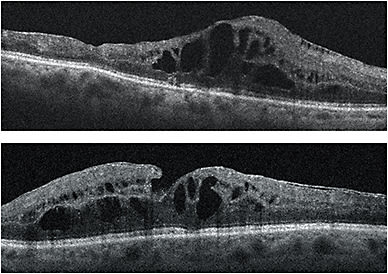

In 2015, because intraretinal fluid persisted in both eyes despite significant exposure to anti-VEGF agents and the dexamethasone intravitreal implant, I considered Iluvien to be the next logical step. The patient qualified for on-label use of Iluvien because she didn’t experience a significant increase in IOP with the dexamethasone implant; her IOP didn’t exceed 20 mmHg while that implant was in place. Within 2 months of bilateral Iluvien implantation, DME resolved in both eyes and visual acuity improved from 20/70 to 20/50 OU (Figures 1 and 2). In the first 10 months since implantation, her IOP has not exceeded 20 mmHg. The success of Iluvien in this case where other steroids had failed may be due to its unique stoichiometry. •